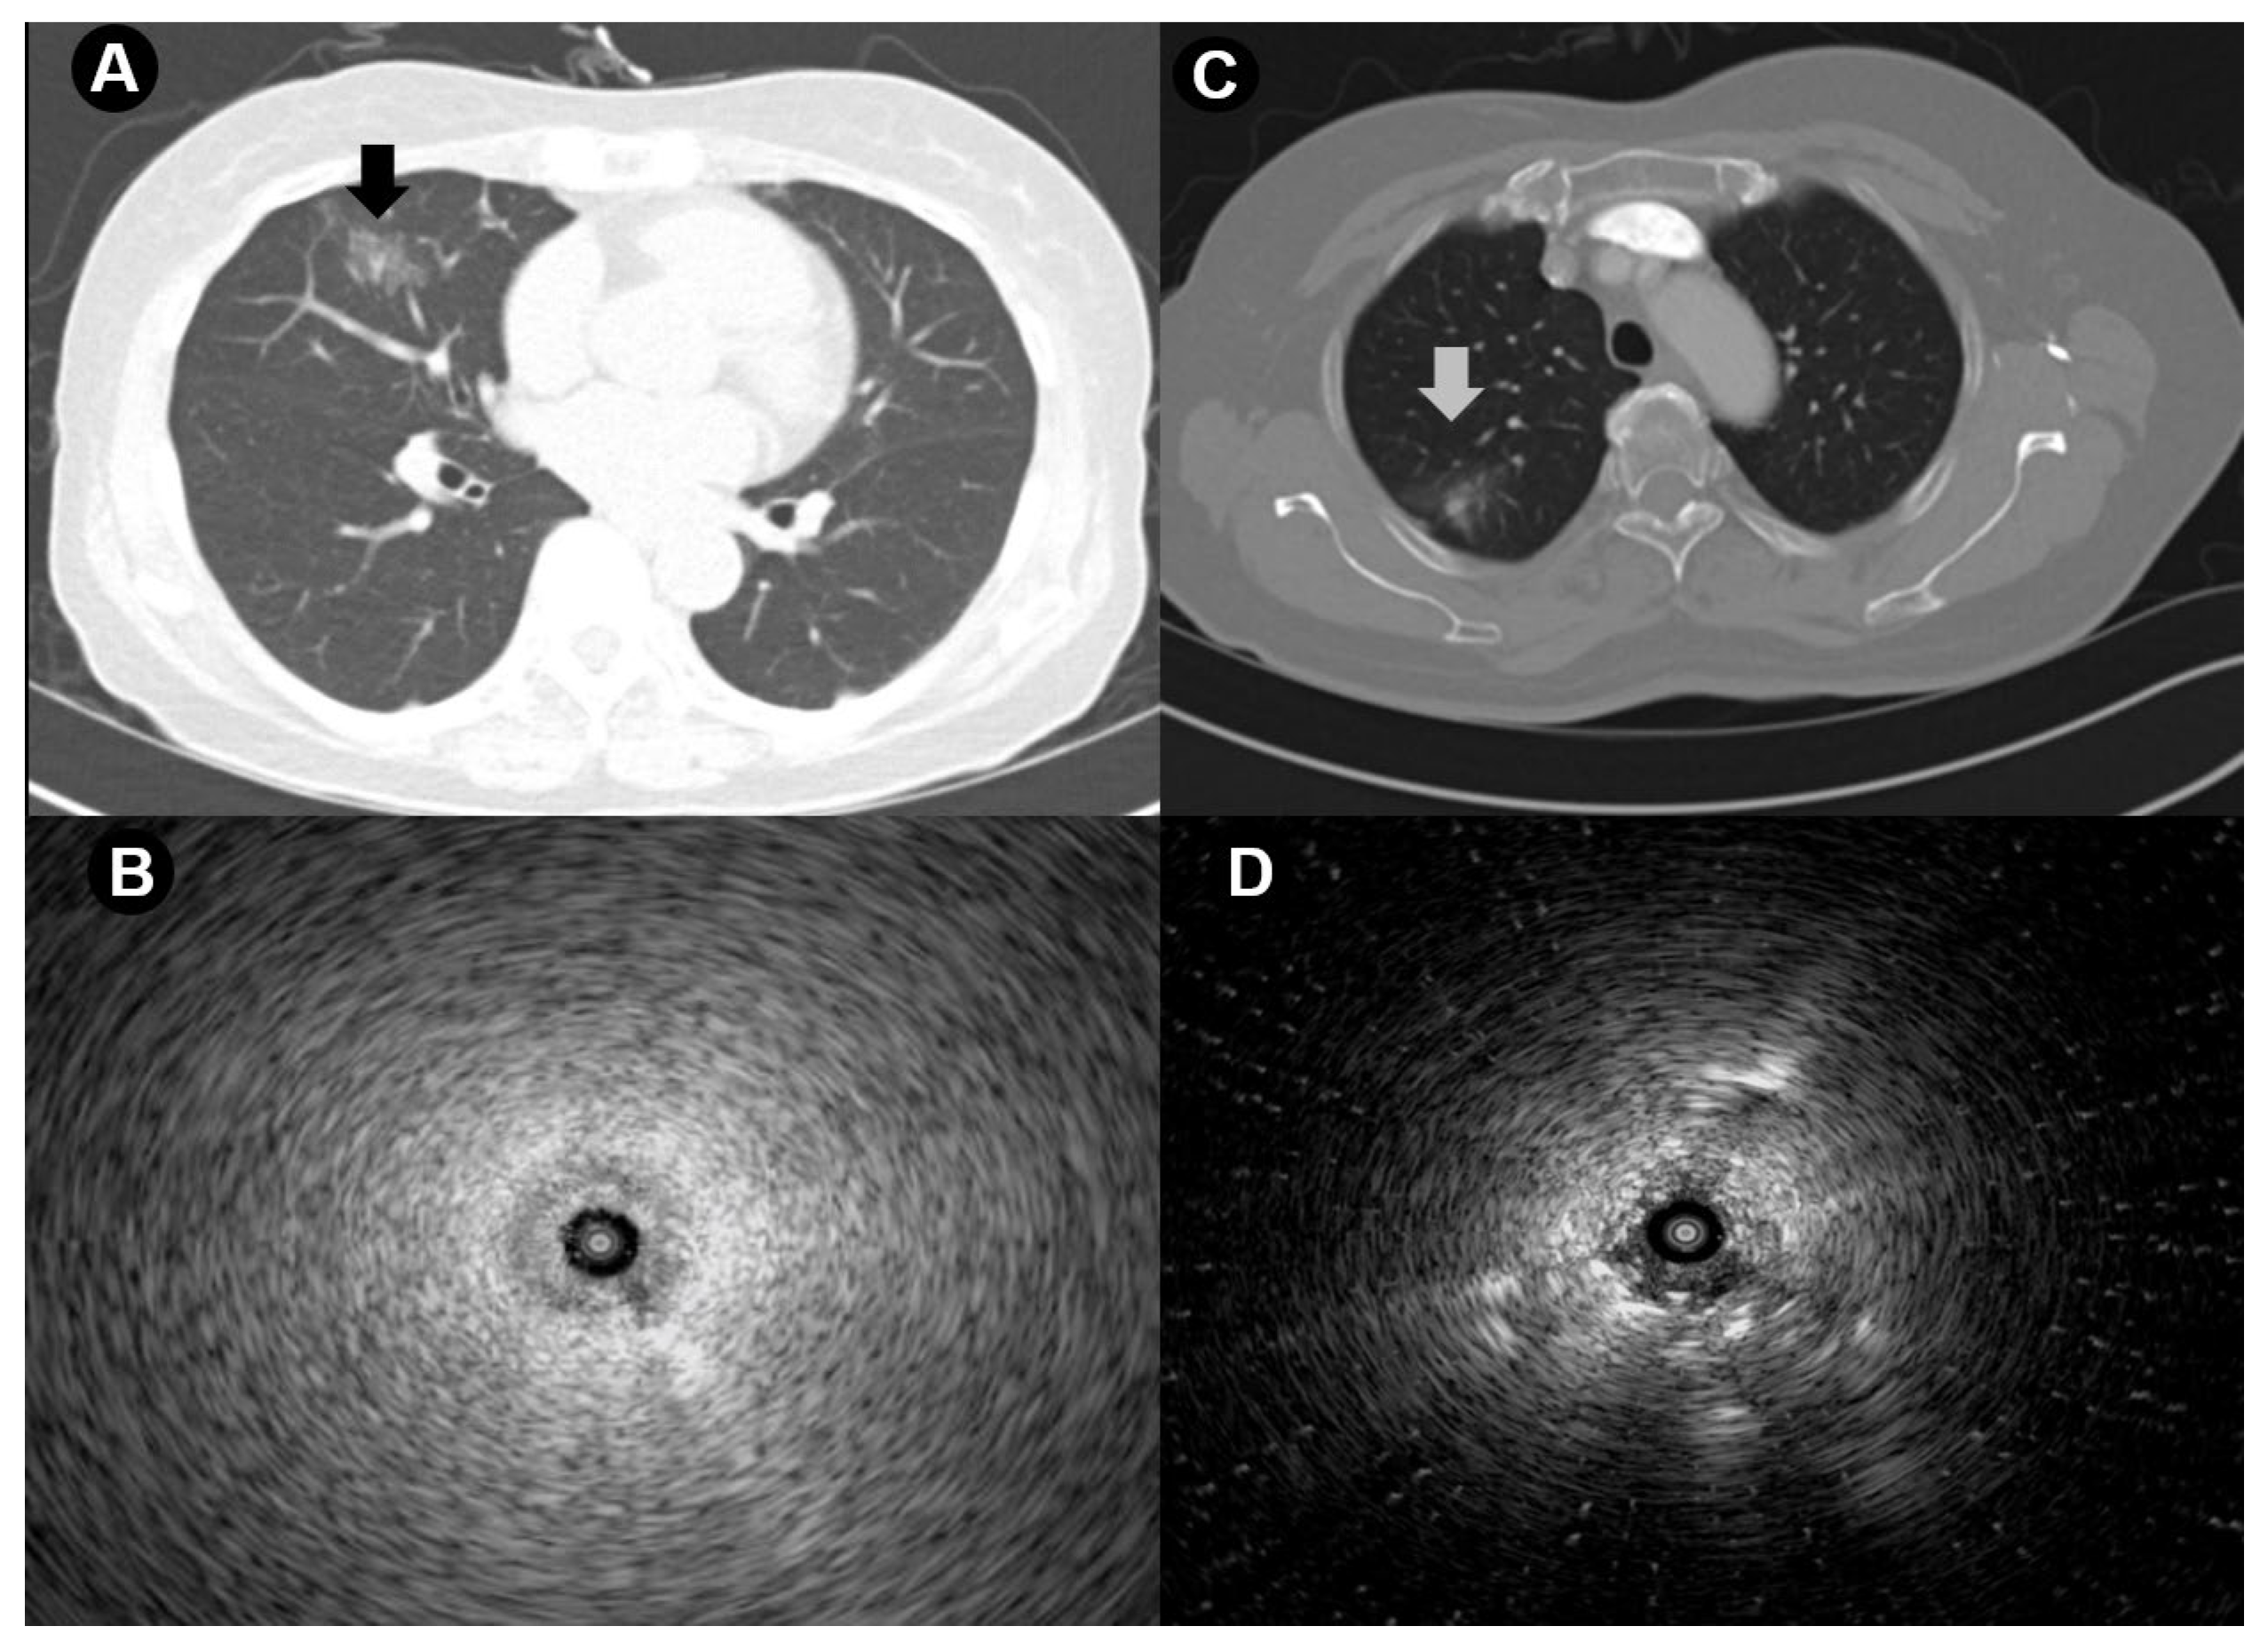

- Izumo, T.; Sasada, S.; Chavez, C.; Matsumoto, Y.; Tsuchida, T. Radial endobronchial ultrasound images for ground-glass opacity pulmonary lesions. Eur. Respir. J. 2015, 45, 1661–1668. [Google Scholar] [CrossRef]